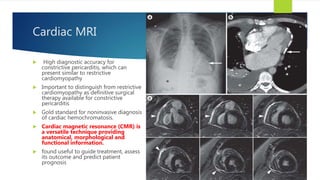

Cardiac MRI

 High diagnostic accuracy for

constrictive pericarditis, which can

present similar to restrictive

cardiomyopathy

 Important to distinguish from restrictive

cardiomyopathy as definitive surgical

therapy available for constrictive

pericarditis

 Gold standard for noninvasive diagnosis

of cardiac hemochromatosis.

 Cardiac magnetic resonance (CMR) is

a versatile technique providing

anatomical, morphological and

functional information.

 found useful to guide treatment, assess

its outcome and predict patient

prognosis

30